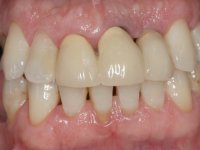

Endodontic treatments were performed and a metalic non screwed intra radicular post was placed on tooth 1.1. An alginate impression was made for laboratory confection of a reinforced acrylic provisional bridge, with teeth 1.1 and 2.2 as abutments and 2.2 as a pontic. After preparation of tooth 1.1 and root preparation of 2.1, the bridge was relined in mouth with self-polymerizable acrylic using a metal post for further retaining the prepared root canal on 2.1. Tooth 2.2 was cut at the gingival level to function as support. In the same session, the impression of the root canal of the 2.1 was made for the laboratory confection of a cast post and core. A double mixture technique with plastic tutor was used after previous canal vaseline with endodontic file and cotton. The provisional bridge was provisionally cemented and the cast post and core was made in the laboratory. Cast post and core cementation was made with resin-reinforced glass ionomer cement and the provisional bridge had to be readjusted to the new situation by removing the post at the site of 2.1. After careful surgical planning, a dental implant was placed, simultaneously with extraction of the root of tooth 2.2. The provisional bridge was placed by resting on the healing screw placed in the implant. The respected osteointegration period was 12 weeks, during which the provisional bridge was relined twice. After complete maturation of hard and soft tissues, definitive impressions were made. The gingival retraction technique was applied with an impregnated retraction cord and impression was performed using double mixture, open tray impression technique. A custom precious metal abutment implant was prepared in the lab, along with 3 metal caps to be used as infrastructures for the metal ceramic crowns. Particular care was taken in the confection of the cervical finishing line of the implant abutment, in order to follow the soft tissues emergence profile. Proof of infrastructures was done in the mouth being evaluated clinically and imagiologically. Collection of color information was done by the ceramist at the office. Ceramic was applied in the laboratory and the finished work was placed in the mouth after approval by the patient. Definitive cementation was made with resin-reinforced glass ionomer cement, and the first crown to be cemented was that of the implant, to facilitate removal of the excess.